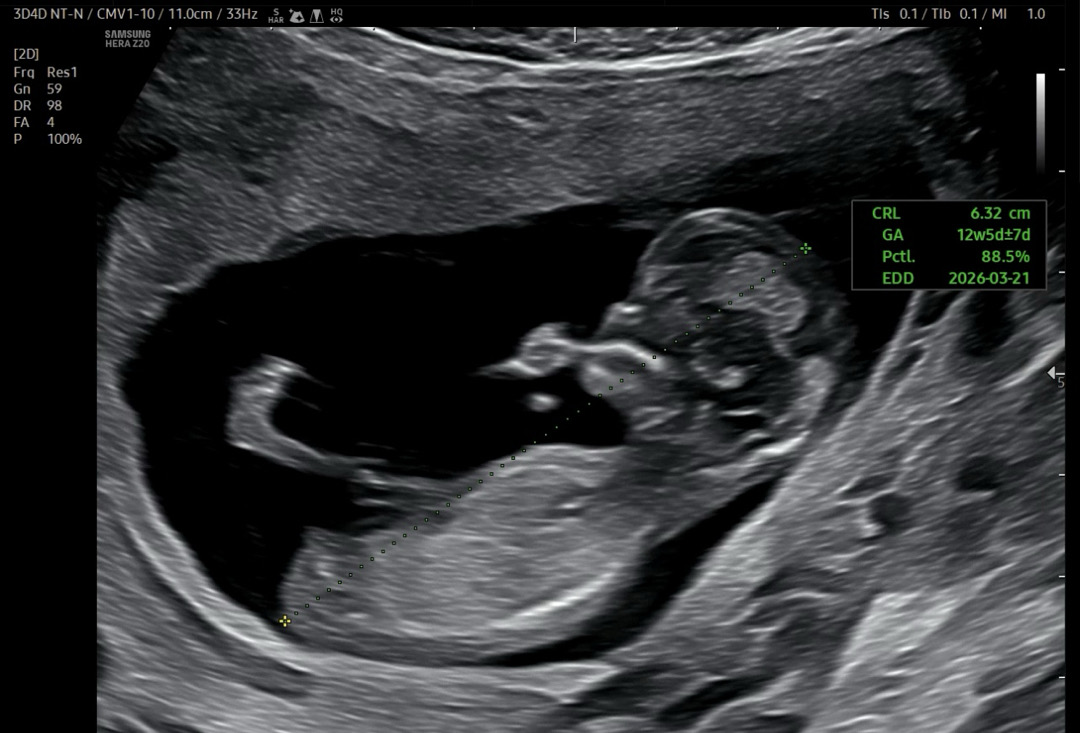

램지법으로 딸이요

각도법 고수님들 봐주세요

아들일까요... 딸일까요...?